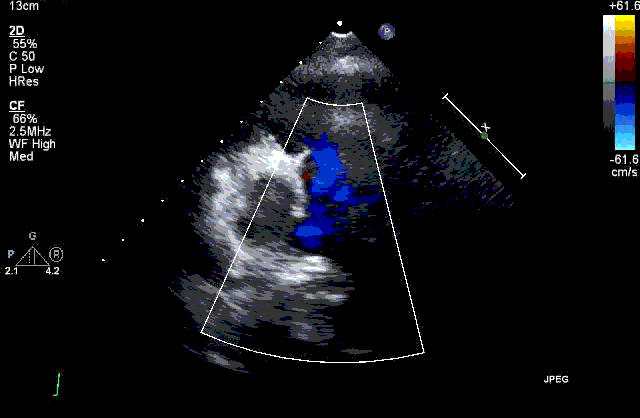

اکو قلب از امواج فراصوت استفاده می کند و تصاویر متحرکی از قلب را بر روی مانیتور به پزشک نشان می دهد تا پزشک عضله قلب و دریچه ها را ارزیابی کند. به اکو قلب اکوکاردیوگرافی و یا سونوگرافی تشخیصی قلب نیز گفته می شود. اکوکاردیوگرافی تصاویر حفرات قلبی، دریچه های قلبی، دیواره ها و عروق قلب را نشان می دهد.

از طریق اکو قلب سلامت قلب، دریچه ها، عروق قلبی، وجود بیماری های قلبی و ارزیابی پاسخ به درمان بررسی می گردد. پزشک بعد از انجام اکوکاردیوگرافی گزارش را به شما تحویل می دهد و نتیجه را برای شما توضیح خواهد داد.

- کارایی دریچه های قلبی (آئورت، پولمونری، سه لختی و دولختی یا میترال)

- نارسایی دریچه های قلبی

- تنگی دریچه های قلبی